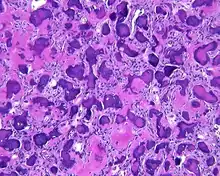

By microscopic evaluation, the tumors are composed of a variably cellular stroma make up of spindled to stellate fibroblast-like cells. Within this stroma, are numerous small, rounded, mineralized collagenous ossicles and immature osteoid. Many times the curved-shaped bone fragments have a collagenous rim around them. Ossicles may fuse to form much large mineralizations. Cementum-like psammomatous bodies (cementicles) may also be present. Osteoblastic rimming is not uncommon. Occasionally, giant cells and even mitoses are seen.[1][3]